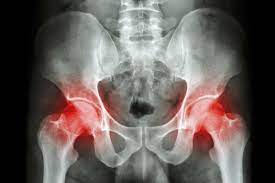

The Surgical Treatment Of Pelvic Bone Metastases from static-01.hindawi.com Causes of bone lesions include infections, fractures, or tumors.  bone cancer in the hip can cause pain, limping, fractures of the bone, and hypercalcemia , a condition in which there is too much calcium in your blood. Your bone metastases may be: The abdomen may feel very full or heavy, and the person may also have lower back pain. Or, the cause of a symptom may be a different medical condition that is not cancer. While scientists need to carry out more research into the precise cause of bone cancer, the american cancer society state that there is a range of risk factors for bone cancer, including genetics. When this happens, the pelvic pain is there simply because your pelvis is having trouble holding up to the added stress. Chondrosarcoma starts in cartilage tissue lining joints and the ends of bones.the most common sites for it are the pelvis, upper leg, and shoulder.

Bone And Soft Tissue Tumors Of Hip And Pelvis European Journal Of Radiology from els-jbs-prod-cdn.jbs.elsevierhealth.com Cancer cells that have spread to the bone can damage the bone and cause symptoms. Although cancer can occur anywhere in the body, in cats it usually involves the limbs or any of the bones connecting to the spine such as the ribs, pelvis, and skull. When cells within the bone start to divide uncontrollably, they are sometimes called bone tumors. When a bone tumor grows, it presses on healthy bone tissue and can destroy it, which causes the following symptoms: Persistent or unusual pain or swelling in or near a bone can be caused by cancer or by other conditions. These symptoms might indicate that the tibial tumor is metastatic and the primary tumor may be located elsewhere in the body 2. Tumors may occur in any bone in the body. Bone metastasis can cause pain and broken bones.